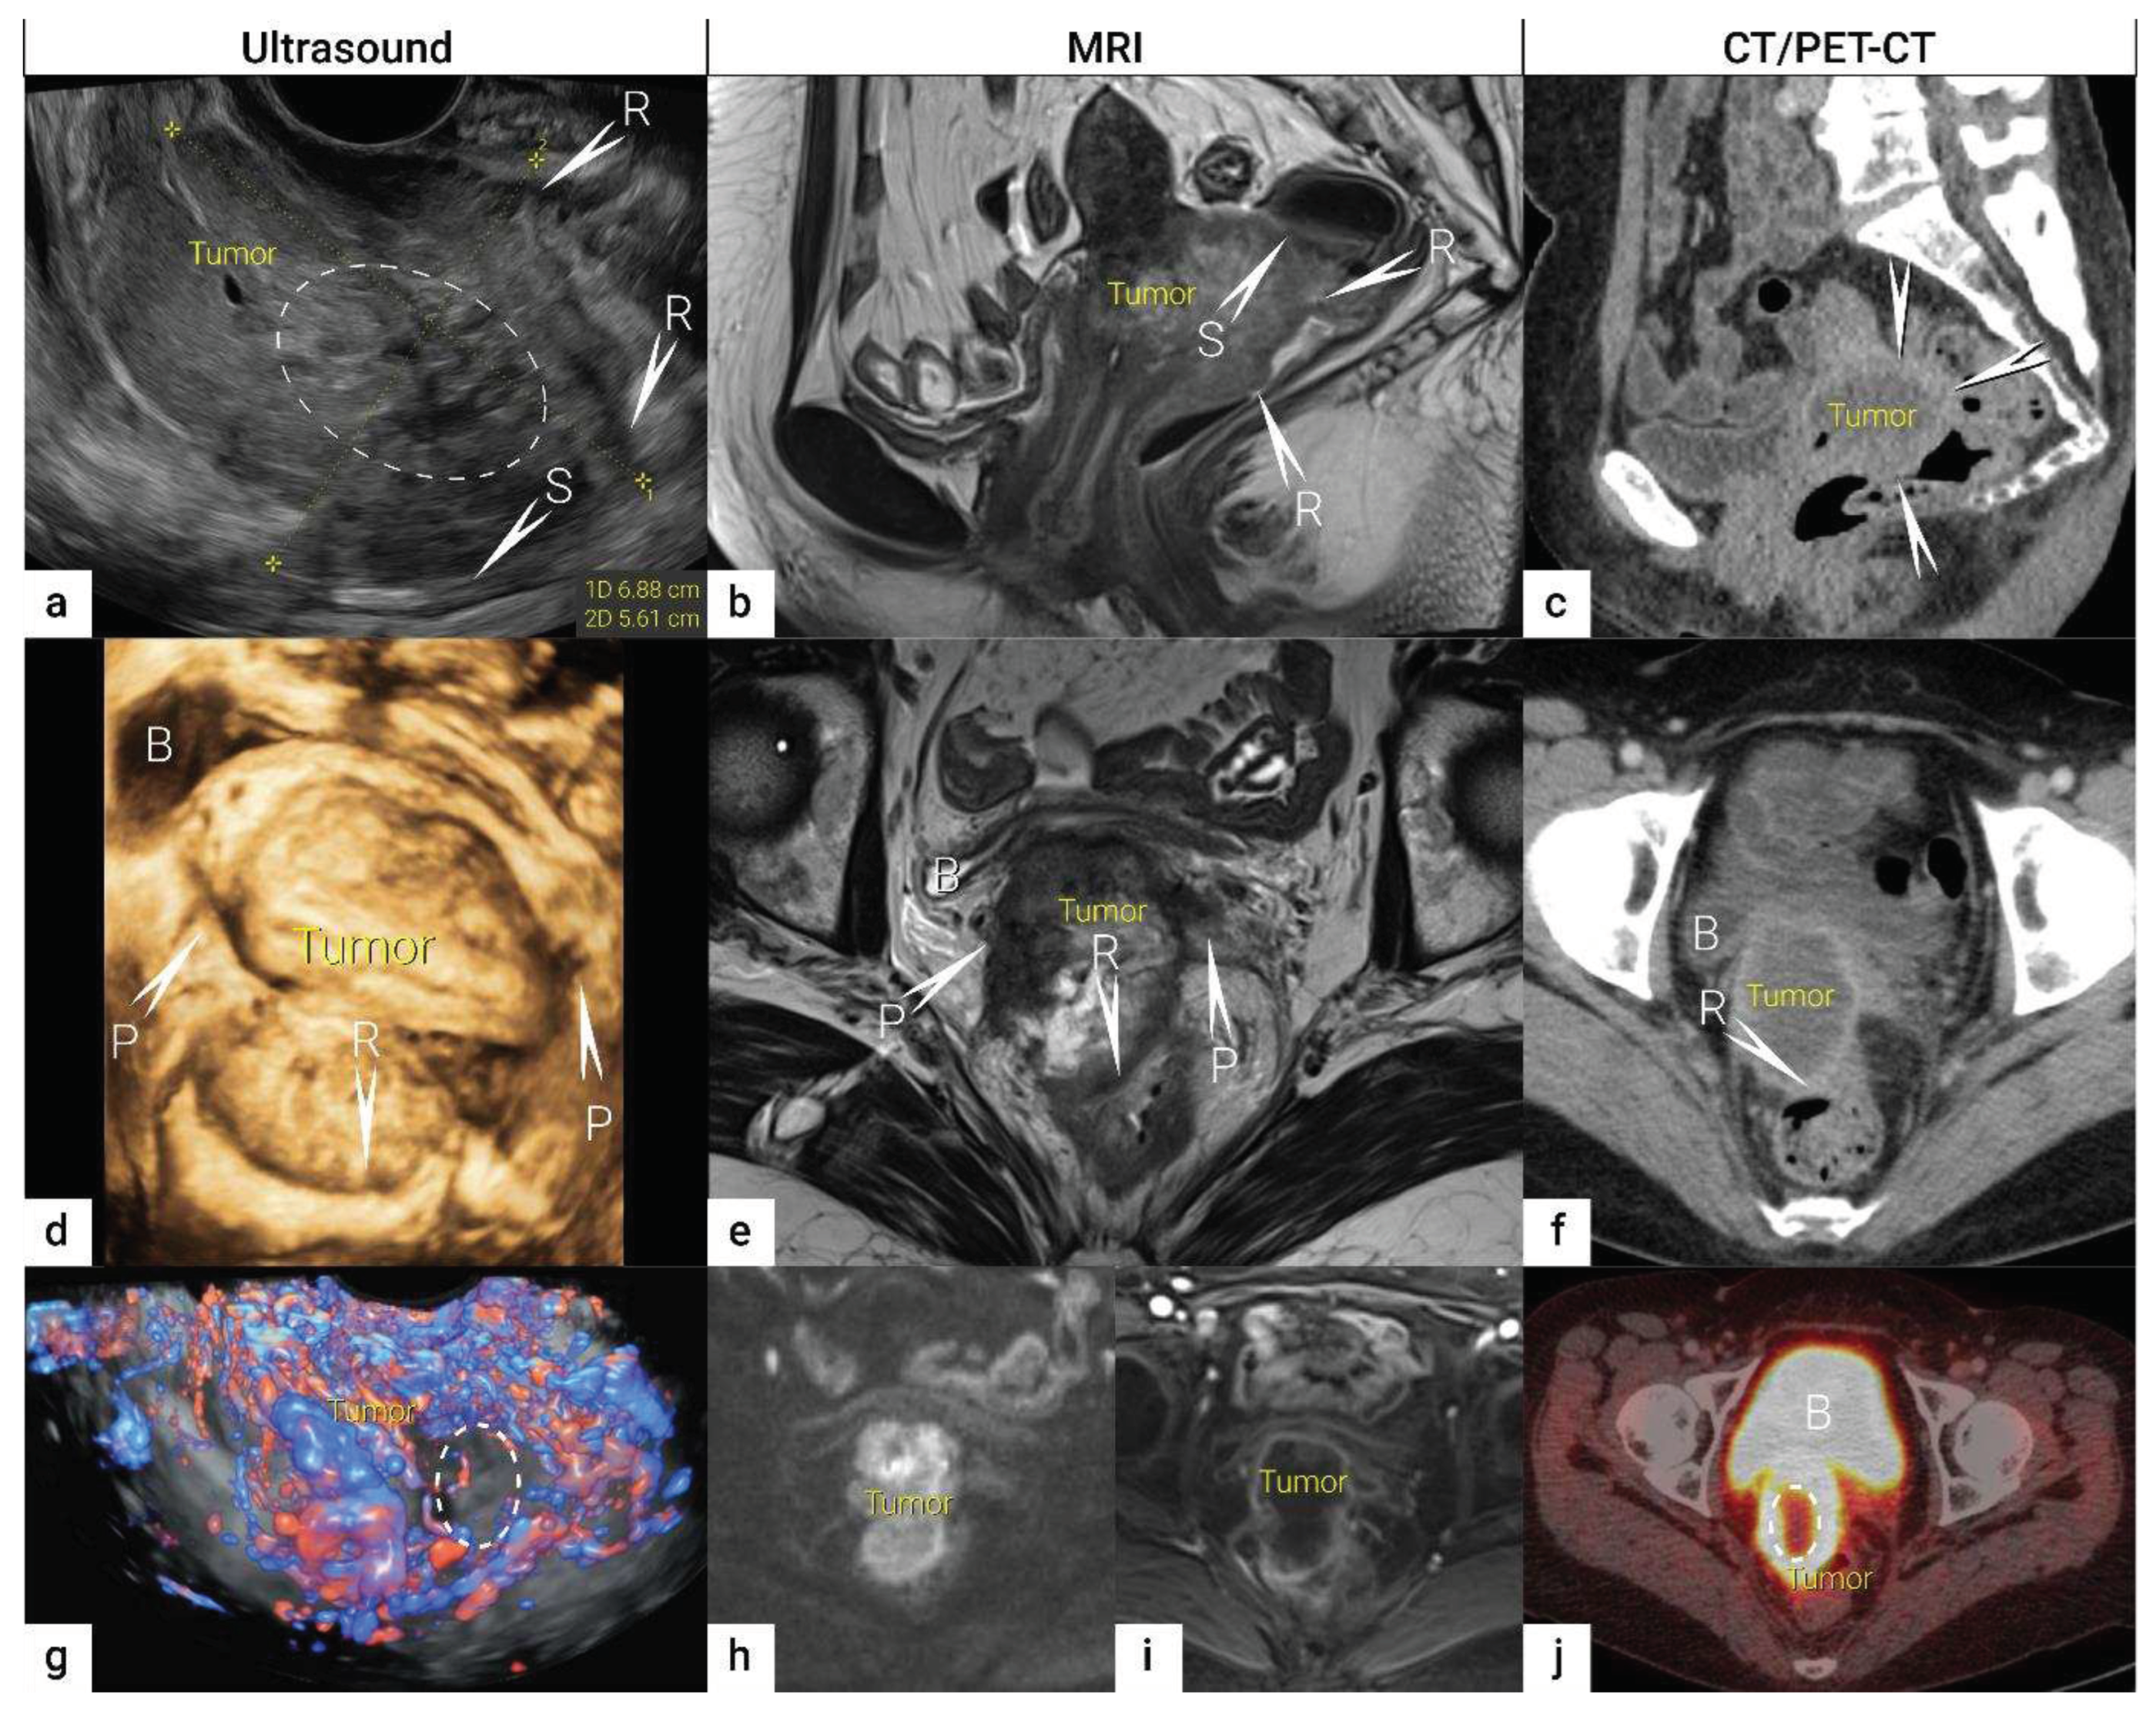

| IB | Carcinoma with deepest stromal invasion>5 mm, limited to the cervix uteri with size measured by maximum tumour diameter. | US: Highly vascularized hypoechogenic (squamous-cell carcinoma) or iso- / hyperechogenic lesion (adenocarcinoma) with intact hyperechogenic pericervical fascia and positive sliding sign between tumour and bladder/rectum. MRI: Tumour has intermediate to high signal on T2W images. Dynamic CE-T1W images depicts tumour as hyperintense in the arterial phase and iso- or hypointense in the venous phase. Tumours characteristically exhibit restricted diffusion on DWI (hyperintensity on high b-value images and low intensity on the ADC maps). Tumor does not disrupt the hypointense peripheral stromal ring (best seen on T2W images). |

| T2 | II | Carcinoma invades beyond the uterus but does not extend to the lower one-third of the vagina or to the pelvic wall | Tumour extends beyond the cervix. Infiltration of upper two-third of vagina or pericervical fascia by US or MRI. Confident diagnosis of parametrial invasion is made in the presence of the spiculated tumor-parametrial interface, soft tissue mass in parametrium, encasement of periuterine vessels, and ureter. |

| T2b | IIB | Parametrial tumour invasion but no pelvic side wall extension | US: Tumour infiltrates the hyperechogenic pericervical fascia, negative sliding sign, presence of hypoechogenic tumour projections into hyperechogenic parametria. MRI: Tumour disrupts the hypointense peripheral stroma and extends into the parametrium +/- abutting parametrial vessels on T2W images. |

| T4f | IVAf | Tumour invasion into the mucosa of the bladder or rectum (biopsy-proven) or into adjacent organs. | US: Negative sliding sign, hypoechogenic tumour infiltration of bladder / rectal wall up to echogenic mucosa with polypoid tumor seen intraluminally. MRI: Focal or diffuse disruption of the normal T2-low signal intensity wall of the bladder/rectum, irregular or nodular wall, sometimes including an intraluminal tumour mass. Bulous edema sign, which is hyperintense thickening of the bladder mucosa on T2W images, is only an indirect sign of invasion and should not be regarded as T4 unless confirmed mucosal infiltration at cystoscopy. Infiltration of the posterior bladder wall without mucosal infiltration should not be regarded as T4a. |

| N1 | IIIC1 | Regional lymph node metastasis to pelvic lymph nodes only | US: hypoechogenic rounded lymph node without preservation of typical architecture (loss of the nodal core-sign), inhomogeneous echogenicity due to cystic necrosis and calcifications, capsular interruption, grouping of metastatic lymph nodes and others. Hilar flow may still be preserved in a partial nodal involvement with or without transcapsular vascularisation (vessels penetrating the cortex from outside), the latter are usually found in an advanced stage of infiltration. MRI: lymph nodes with maximum transverse diameter>10 mm; capsule irregularity, rounded (as opposed to oval) shape, inhomogeneous signal with signs of necrosis on T2W images (MRI), restricted diffusion (DWI) or increased FDG-avidity (PET-CT) |